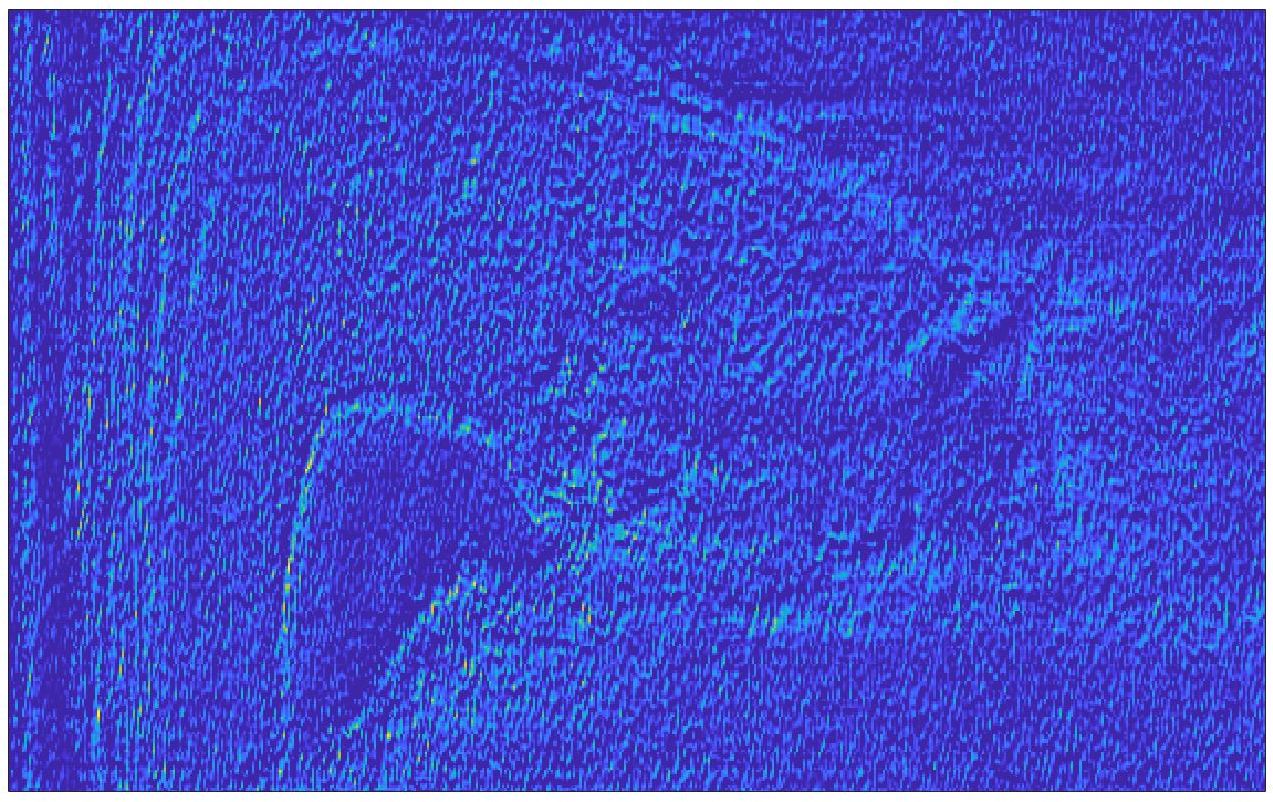

We train each learning-based network (custom-WDSR) with 1.5K images, where the input is the outcome of the selected up-sampling method (i.e., Cubic convolution), and the target is the original high-resolution image. Indeed, input and target images have the same resolution, as the reconstruction of the missing lines has been already performed by Cubic convolution. Figs. 3, 4, and 5 show the results of the network prediction, compared with the input and the target images. Target images correspond to spatial high-resolution images; input images are the outcome of the up-sampling interpolation, which is applied to spatial low-resolution images (i.e., the down-sampling along the lateral direction of high-resolution images); prediction images represent the output of the neural network.

Our framework visually improves the results, in terms of blurring and artefacts. This result is more evident in the magnification of the ear of the foetus (Fig. 3), the mitral valve (Fig. 4), and the mass edges (Fig. 5). Fig. 6 shows the error image of the three anatomical districts with both 2X and 4X up-sampling factors, with the maximum error in the scale . The error is more evident in the contours of the anatomical structures; moreover, the abdominal district shows a smaller error than the cardiac and obstetric ones. We underline that the view for each image is scaled to its maximum, to improve the visualisation of the error.